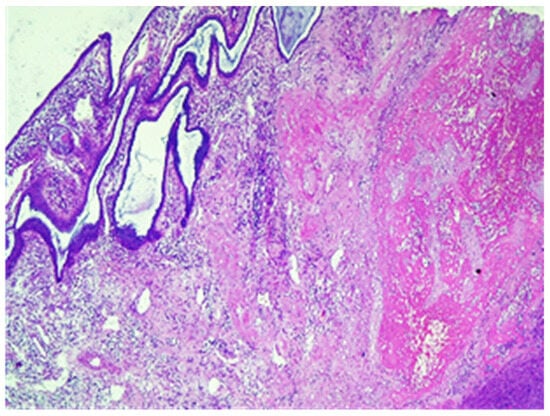

Figure 7.

Chorionic villus without decidua in the thickness of the myometrium, hematoxylin and eosin stain, ×10.